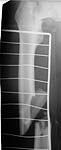

OK, we just fixed all fractures as the patient shows no infection signs. Posterior column was perQ (nice abbreviation) fixed by a screw and a wire, rami - by screws. Then closed locked nailing was performed (i placed a single screw at the upper level - is it commonly acceptable?) and "miss a nail" three cancellous screws to the neck (at the moment we have no more available implants suitable for this lesion like gamma nail etc, so the choice was easy :-). The external fixator left in place as a "local sceletal traction" for a couple of weeks. Acetabular, femoral shaft and neck images attached.